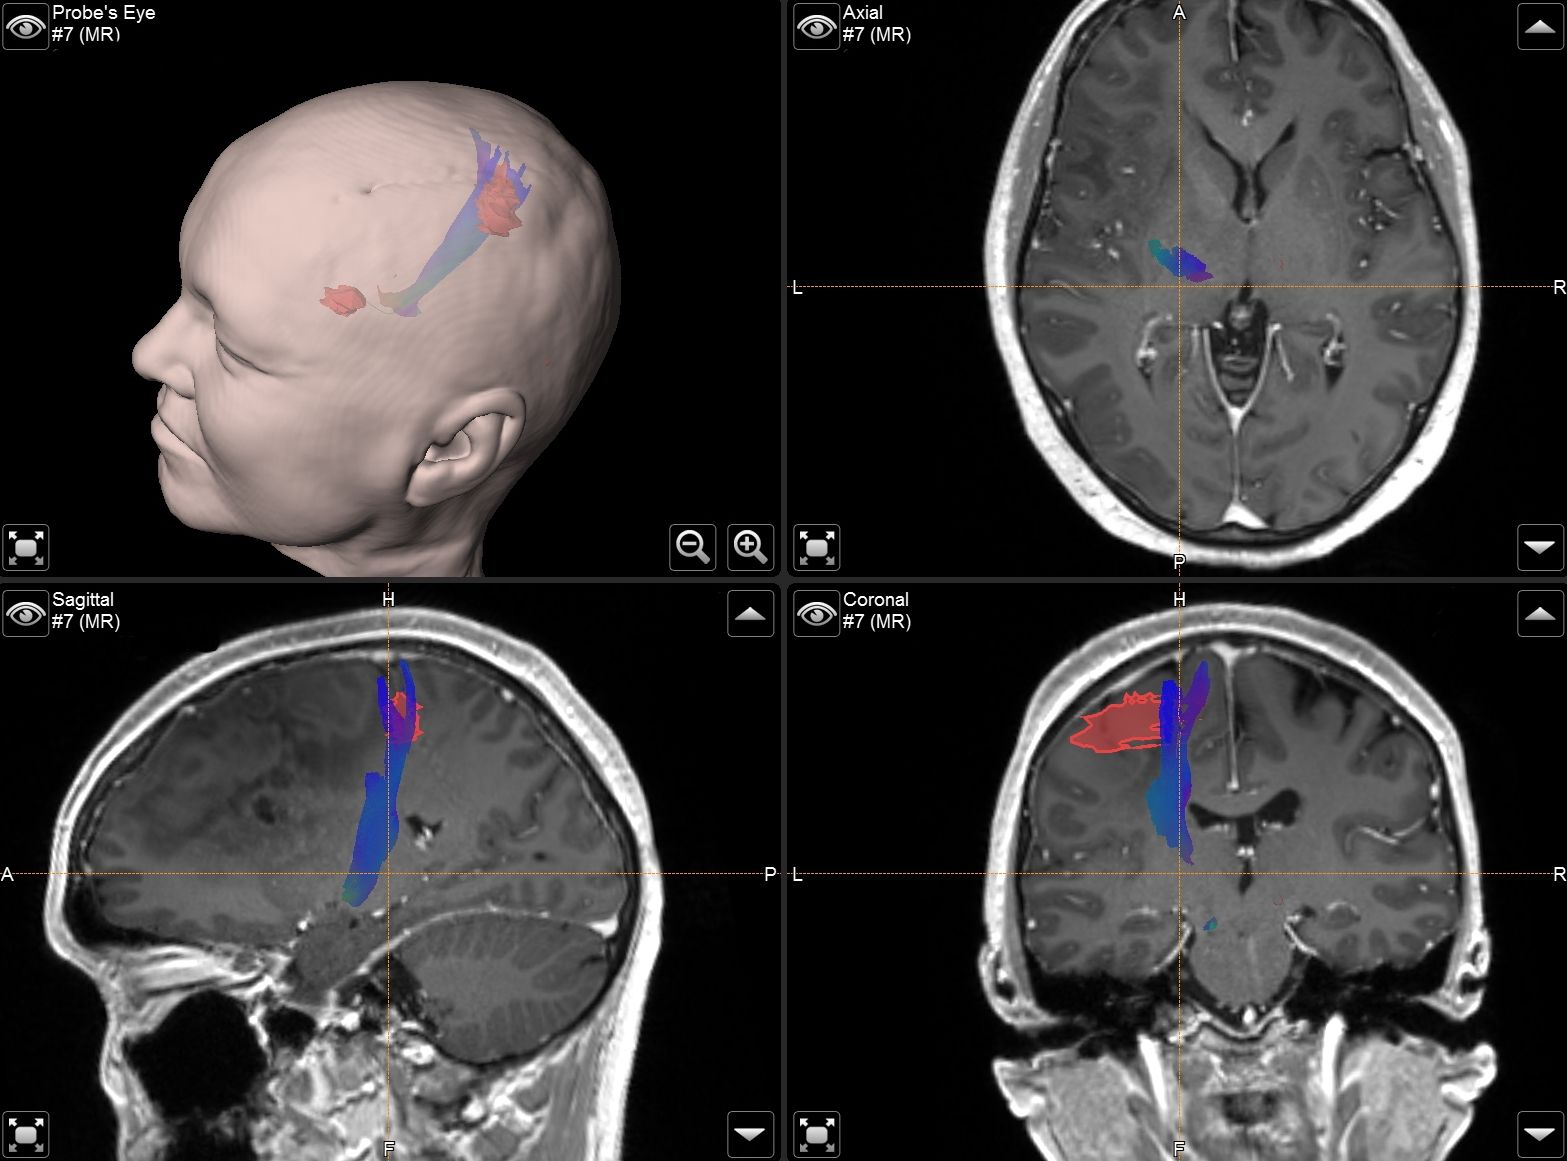

Die Universitätsklinik Tübingen verfügt über hochmoderne mobile Bildgebungssysteme, darunter der robotisch geführte digitale Volumentomograph Loop-X der Firma Brainlab sowie ein mobiler 3D-C-Bogen der Firma Ziehm. Diese fortschrittlichen Systeme ermöglichen intraoperativ eine präzise 3D-Rekonstruktion des Kopfes oder der Wirbelsäule. Für die Kopf- und Wirbelsäulenchirurgie kann mithilfe dieser Technologien ein Navigationsdatensatz erstellt werden, der eine hochpräzise Navigation gewährleistet. So können beispielsweise Schrauben in der Wirbelsäule exakt platziert und kontrolliert oder Trajektorien für Zugangswege und Probenentnahmen im Kopf definiert werden.